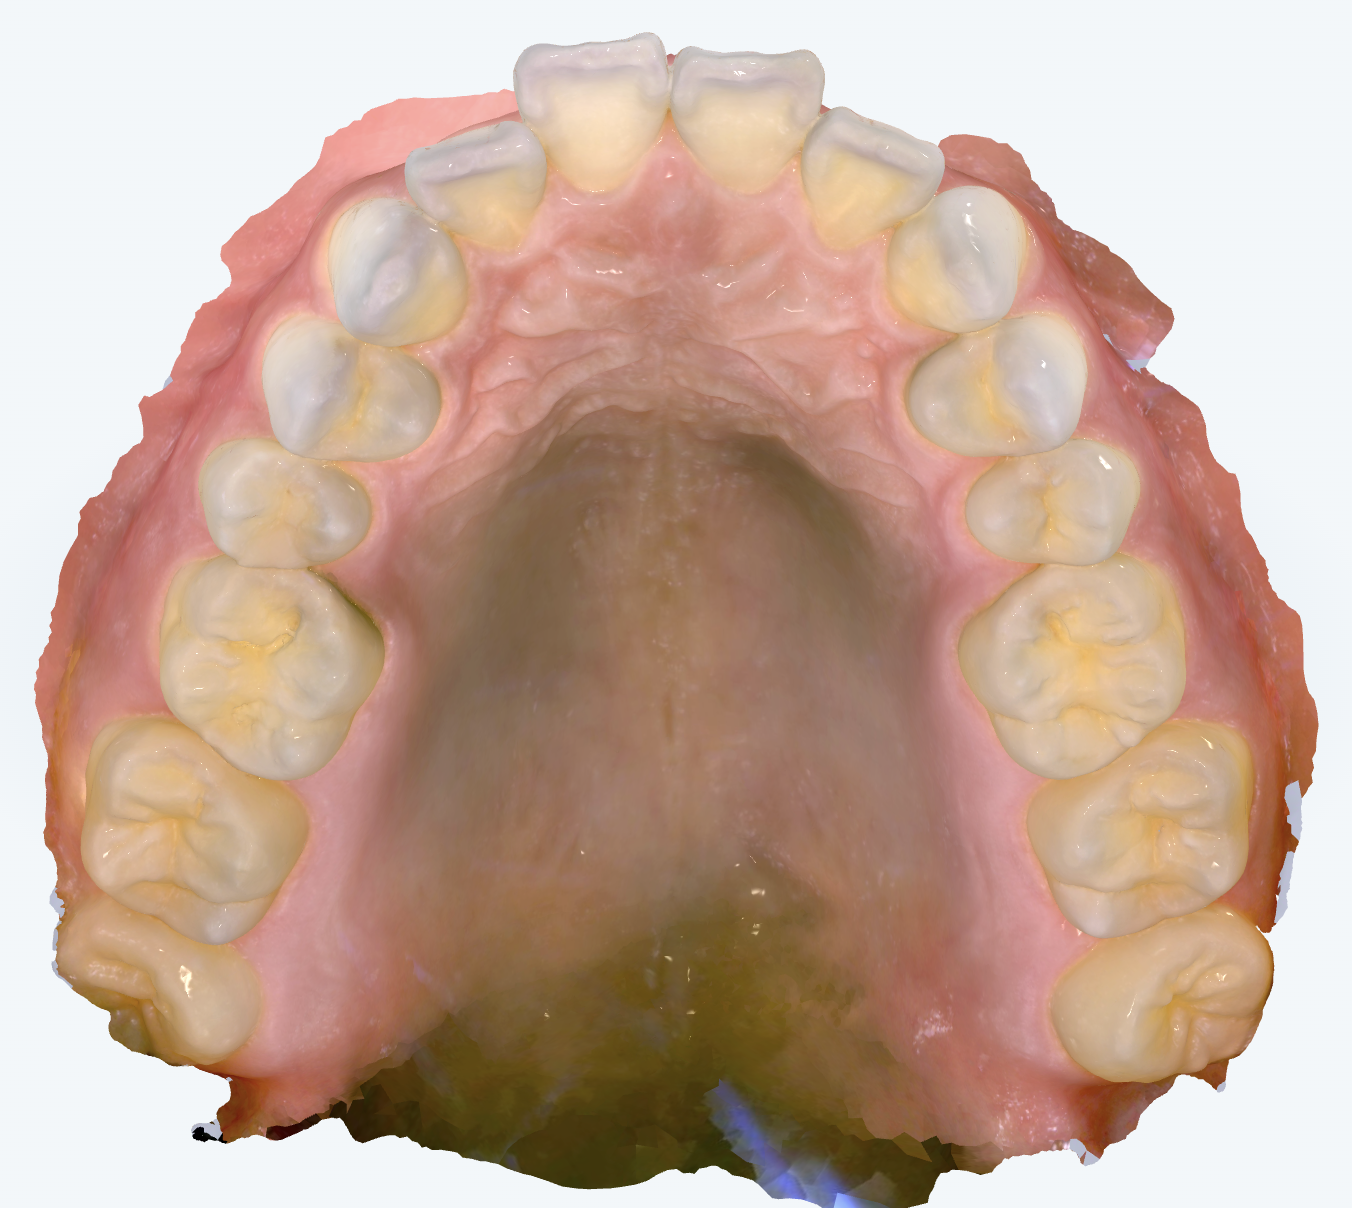

初診時の画像診断

前歯は上顎前突(いわゆる「出っ歯」)の傾向が見られ、歯列全体がV字状にやや前方へ尖っているアーチをしています。前歯の傾斜角は前方への傾きが顕著でした。

また、奥歯のかみ合わせにもズレが見られ、上顎歯列全体が前に位置していることが根本的な原因と考えられました。